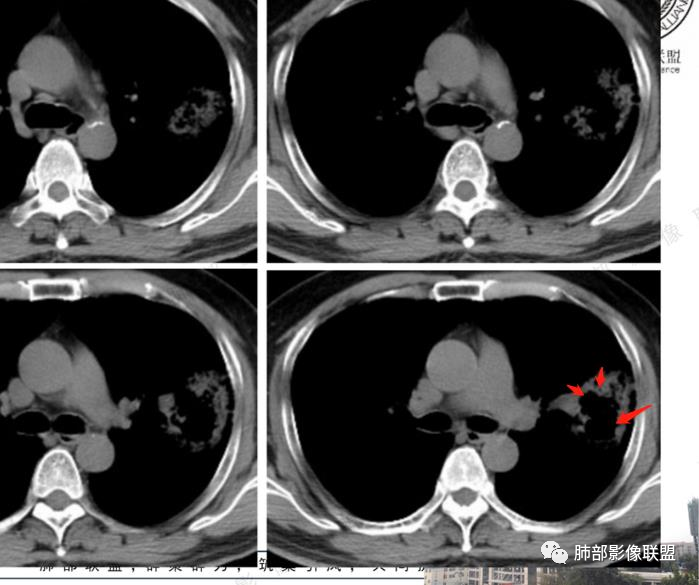

临床病史:男性,51岁,咳嗽咳痰两个月,痰液粘稠,无发热,2型糖尿病病史

化验检查:血象不高,细菌培养结果显示肺炎克雷伯杆菌。

影像所见:左肺上叶尖后段团片状高密度影,边界清楚,其内密度不均,中心呈多发低密度影,与支气管关系显示不清。

治疗过程:抗感染治疗后间隔2月复查,胸片影像病灶稍增大。结合病史首先考虑恶性,肺炎型肺癌可能性大。鉴别肺克及毛霉?非结核分支杆菌肺病?